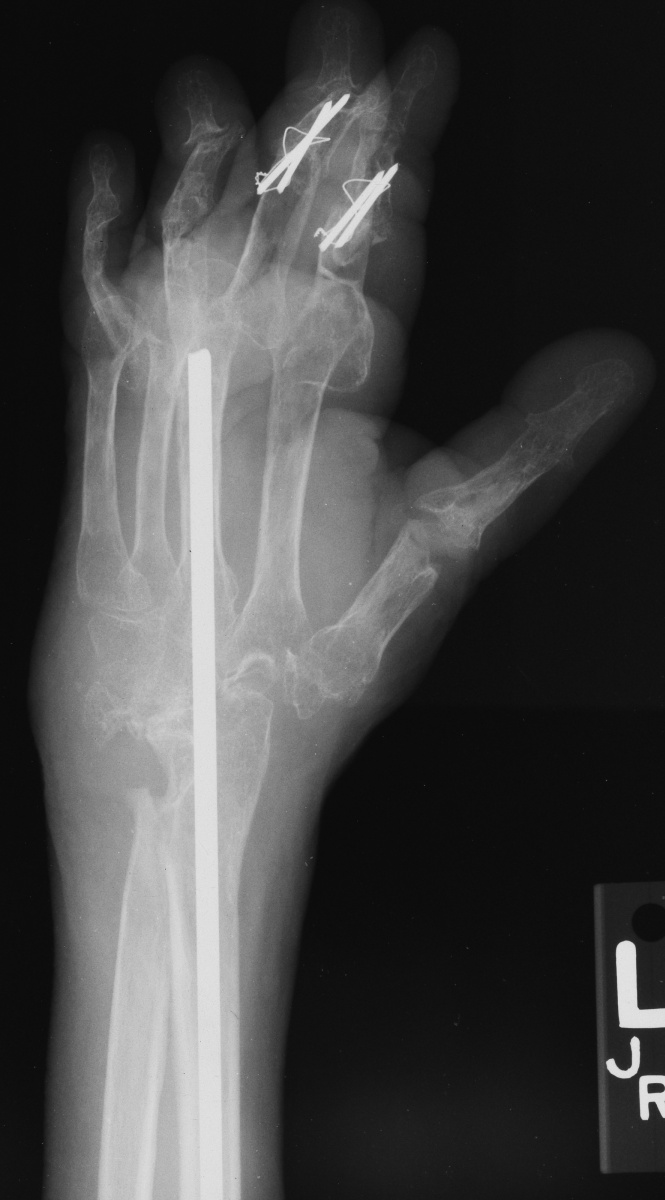

Xrays show radiocarpal collapse, proximal migration of the proximal phalanges, flail PIP joints and loss of the proximal half of the dorsal cortex of the proximal phalanges.

Below are xrays after the first set of reconstructions.

For the second stage of her reconstruction, the index proximal phalanx did not have adequate dorsal cortex to support an implant arthroplasty, and bone graft from the metacarpal head was used to reconstruct this.